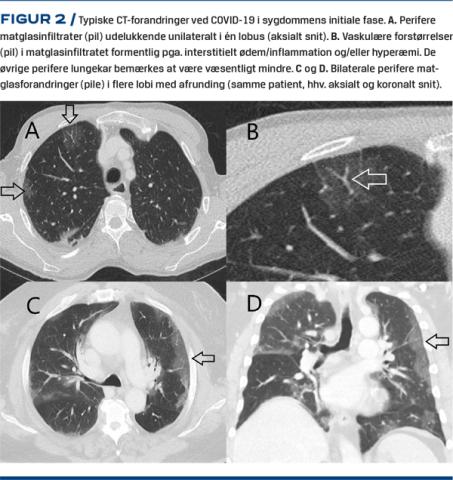

Perifert beliggende matglasinfiltrater (Figur 2A-D) er det hyppigste fund efterfulgt af konsolideringer senere i forløbet (Figur 3C) [5, 8-12]⁠. Der ses typisk vaskulær forstørrelse i matglasinfiltraterne (Figur 2B) [13], hvilket formentlig repræsenterer interstitielt ødem/inflammation peribronkovaskulært og/eller muligvis en øget kardiameter på grund af hyperæmi. Ofte er matglasinfiltraterne afrundede (Figur 2C og D). I nogle tilfælde er de mere centralt beliggende. Multilobær og bilateral placering er hyppigst – særligt når sygdommen progredierer (10,12). Der kan som ved andre pneumoniske sygdomme findes luftbronkogram i infiltraterne [14-16]. Der kan ved progression ses crazy paving(Figur 3B)og retikulering med traktionsbronkieektasier (Figur 3 D) [10, 14, 16, 17] samt reverse halo sign(Figur 3F) [12, 13]. Et perilobulært mønster med arcade-like sign(Figur 3 E) kan også ofte ses, når sygdommen peaker omkring 10-14 dage efter symptomudbrud [18], hvilket indikerer sekundær organiserende pneumoni som det også er set ved lignende virale infektioner som SARS-CoV, MERS-CoV og H1N1-influenzavirus [19, 20]. Derimod ses pleural ansamling, mediastinal lymfeknudeforstørrelse samt pneumothorax sjældent ved COVID-19 [8, 13, 16, 21, 22], og disse fund bør give mistanke om bakteriel superinfektion eller andre sygdomme [7]. I et studie med 424 patienter var pleural fortykkelse, pleuraeffusioner, mediastinal lymfeknudesvulst samt luftbronkogram signifikant hyppigere ved andre typer af viral pneumoni end COVID-19 [13]. Tree-in-bud-forandringer samt kaviterende infiltrater er ikke hyppige [9, 11].